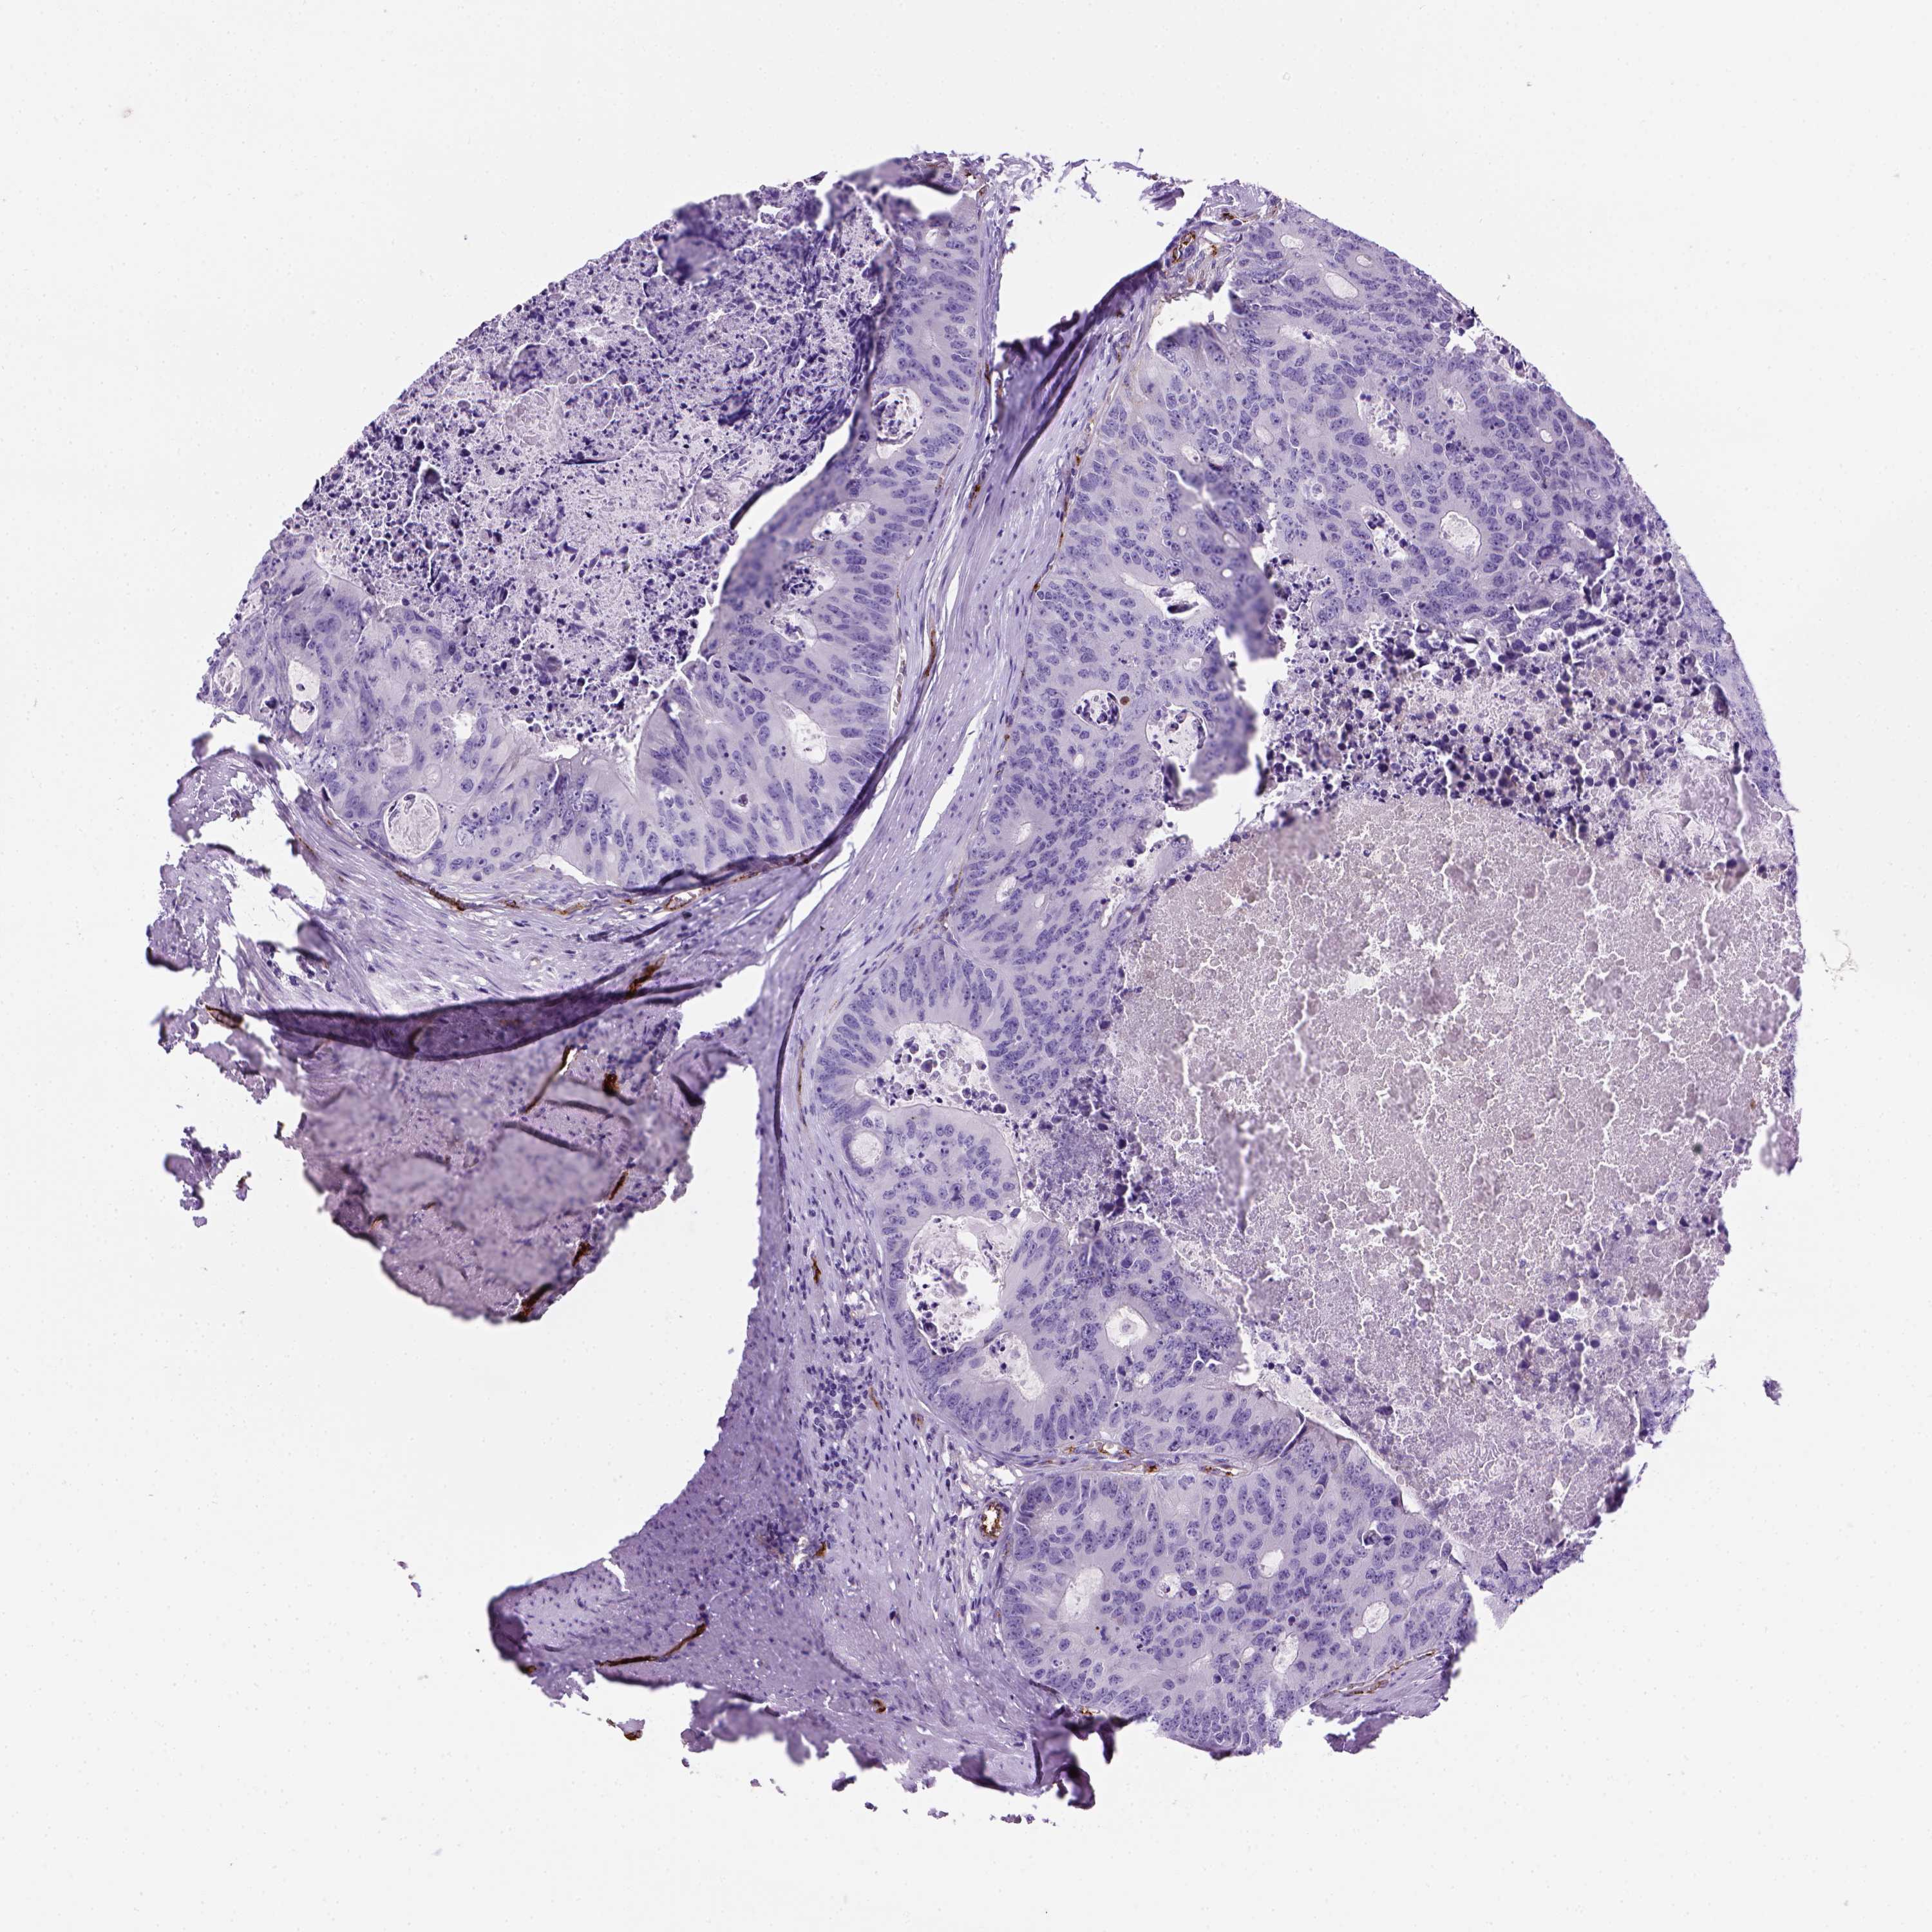

CANCER COLORECTAL CANCER Show tissue menu

COAD TCGA COAD VALIDATION READ TCGA READ VALIDATION PROTEIN COAD CPTAC PROTEIN EXPRESSION

ANTIBODIES

AND

VALIDATION